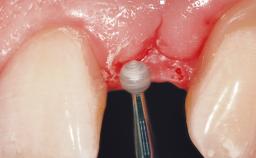

A 56-year-old female patient was referred to the clinic for the functional rehabilitation of her left mandible. The healthy, non-smoking patient presented with loss of retention of crown 35 due to secondary root caries. In addition, she had a single-tooth gap at site 36 with clearly discernible facial atrophy. The panoramic radiograph exhibited crowned teeth 35 and 37, both with a root canal filling. Tooth 37 showed a radiolucent area on the mesial aspect. Tooth 38 did not show any signs of pathology. Based on the clinical and radiographic findings, it was decided to remove root 35 and tooth 37, creating an extended edentulous space with three missing teeth. As requested by the patient, tooth 38 was left in place. The removal of both teeth was done without major flap elevation. The wound margins at site 35 had to be slightly elevated to remove the root remnant.